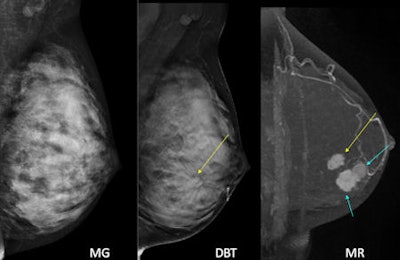

MRI plus mammography has higher sensitivity than digital breast tomosynthesis (DBT) plus mammography, according to an article published in European Radiology. However, DBT still performs better than mammography alone and has a higher positive predictive value (PPV) than MRI.

The research team, led by Dr. Won Hwa Kim from the radiology department at Seoul National University Hospital in South Korea, studied patients who underwent mammography, DBT plus mammography, and MRI plus mammography. They found MRI has the highest sensitivity when the three modalities are compared, although it has a lower PPV than DBT.

Mammography is an imperfect modality for detecting breast cancer, so researchers are always on the lookout for something better. MRI is highly sensitive and thus a possibility. DBT shows promise, but until now, a direct comparison between DBT and MRI has rarely been performed, and the limited data thus far have shown only comparable performance, according to Kim et al (Eur Radiol, 16 September 2015).

The researchers independently reviewed image sets of 172 patients with 184 cancers. They looked at mammography alone (Selenia Dimensions, Hologic), DBT (same system) plus mammography, and MRI (Signa, GE Healthcare) plus mammography. Each image was scored for cancer probability using BI-RADS.